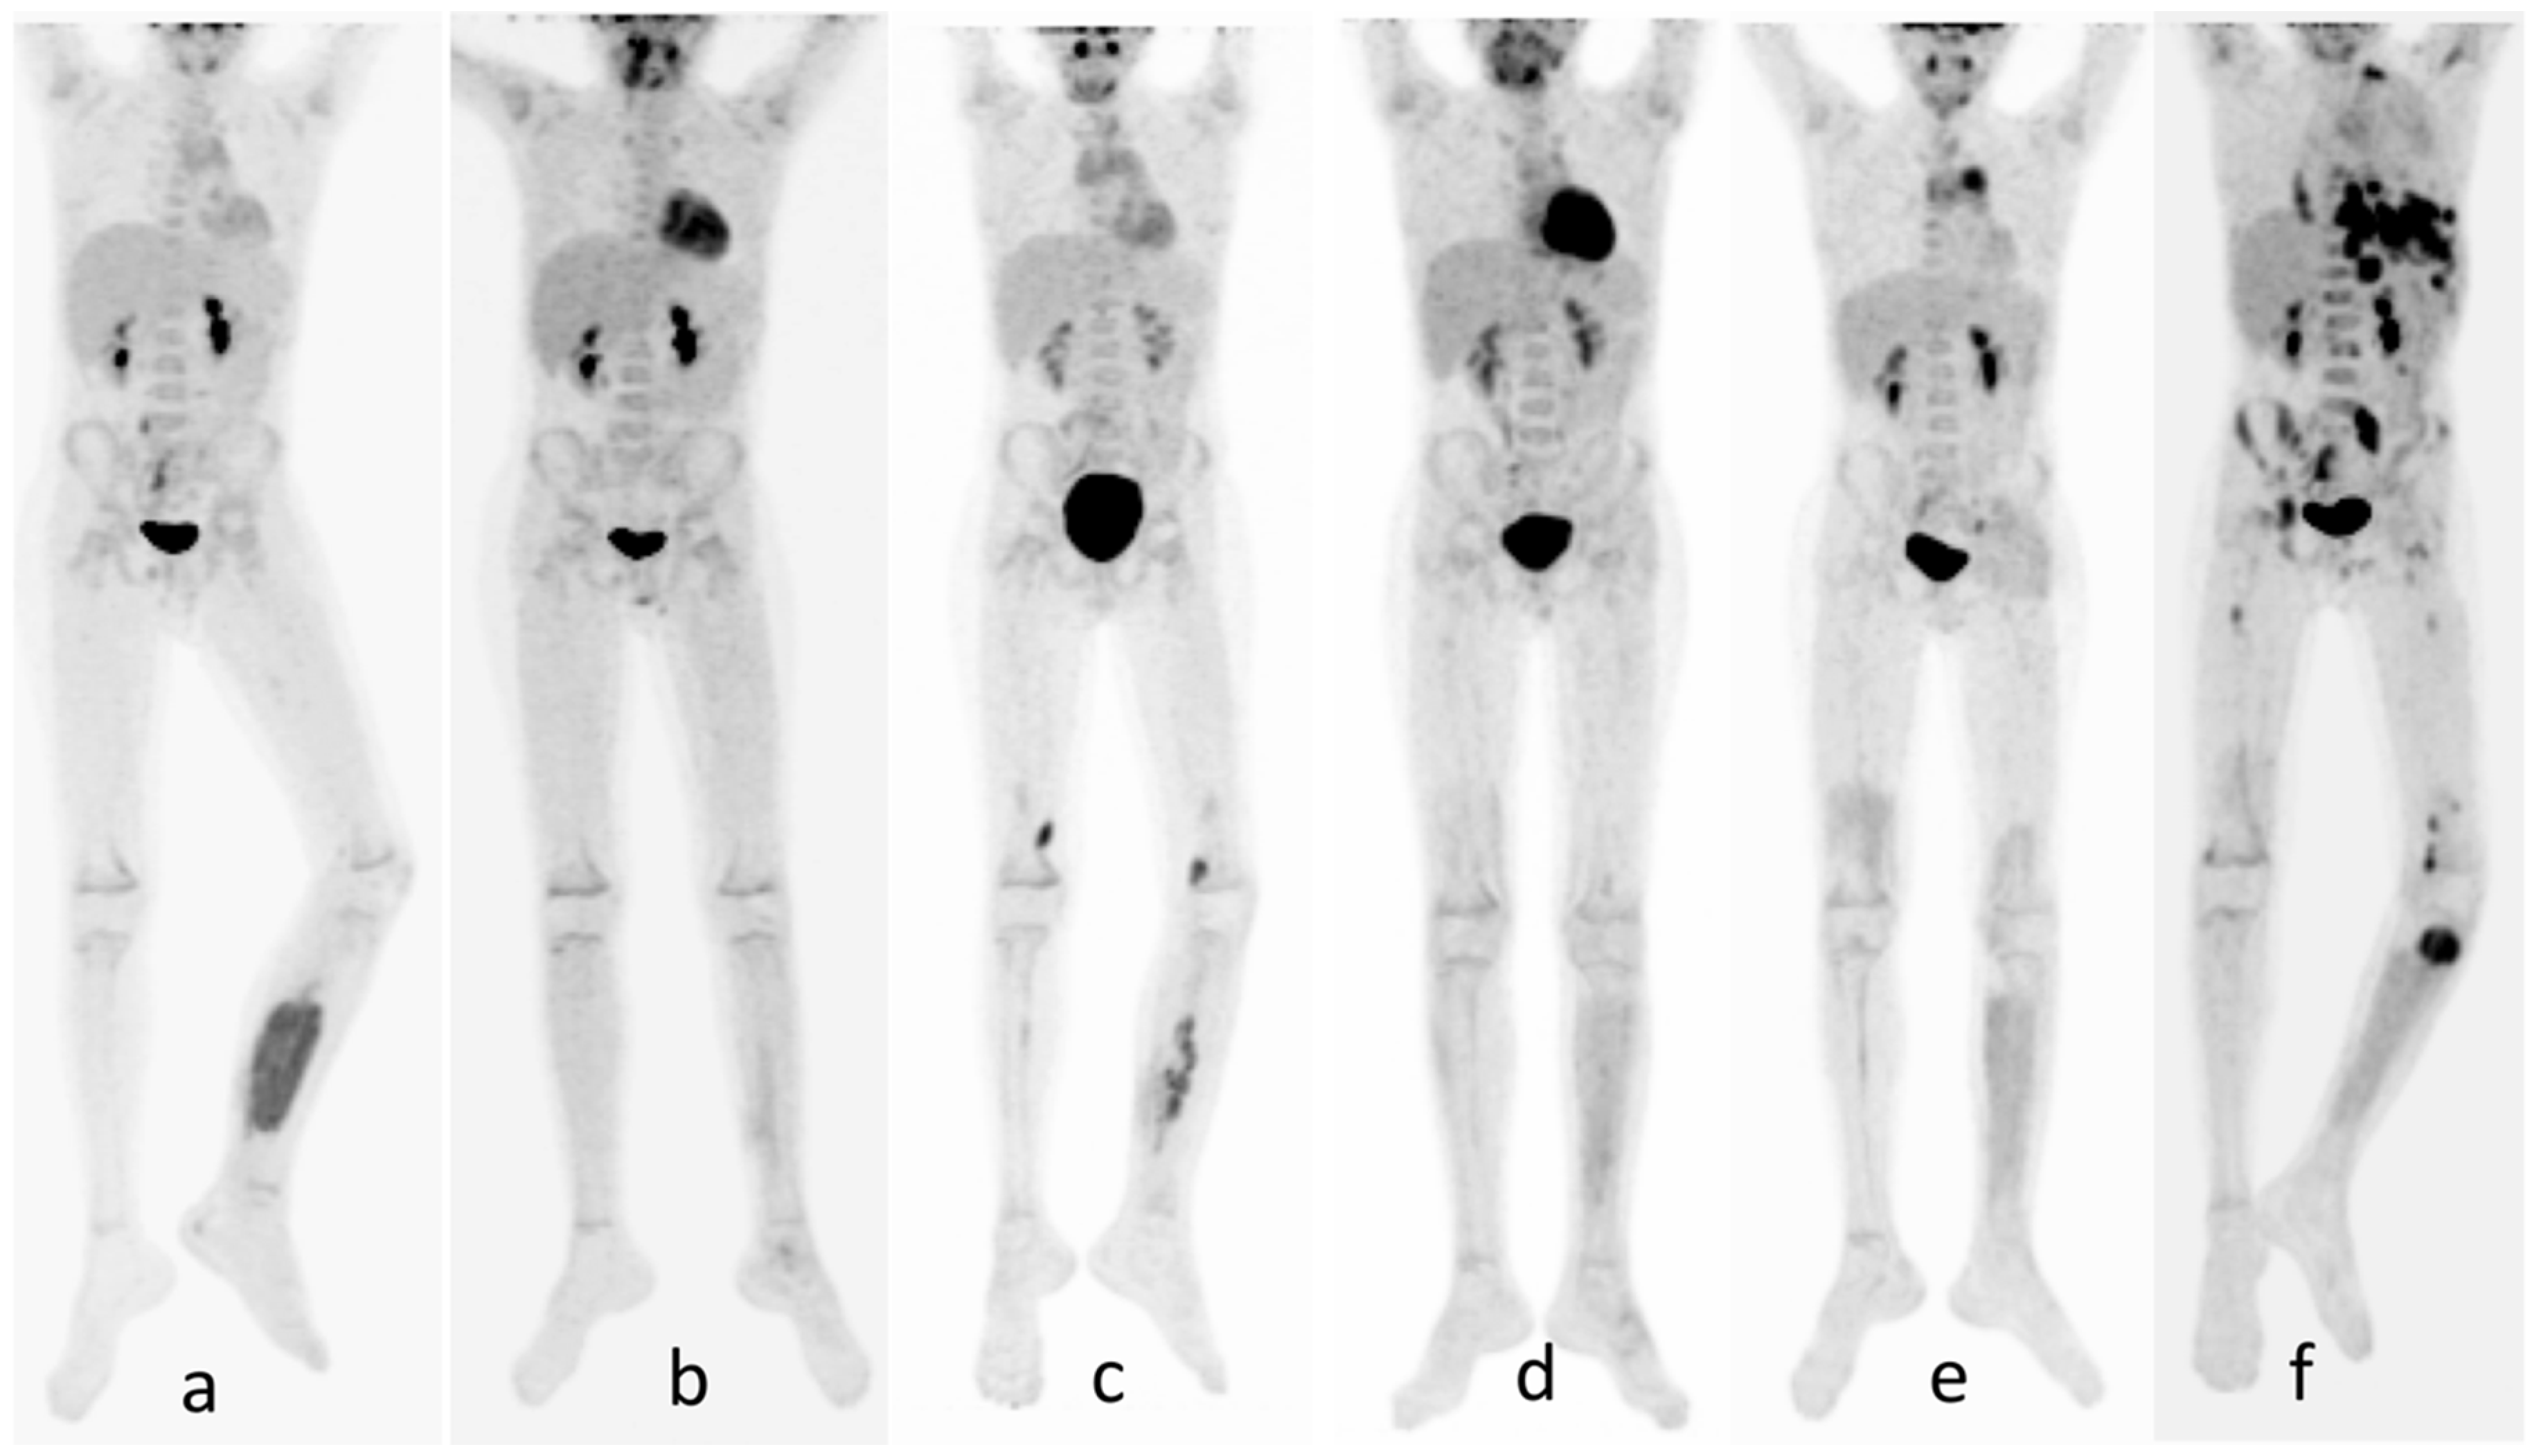

Metastatic Alveolar Rhabdomyosarcoma In A 14-year-old Girl. (a) Axial

www.researchgate.net

www.researchgate.net

rhabdomyosarcoma alveolar metastatic axial obtained